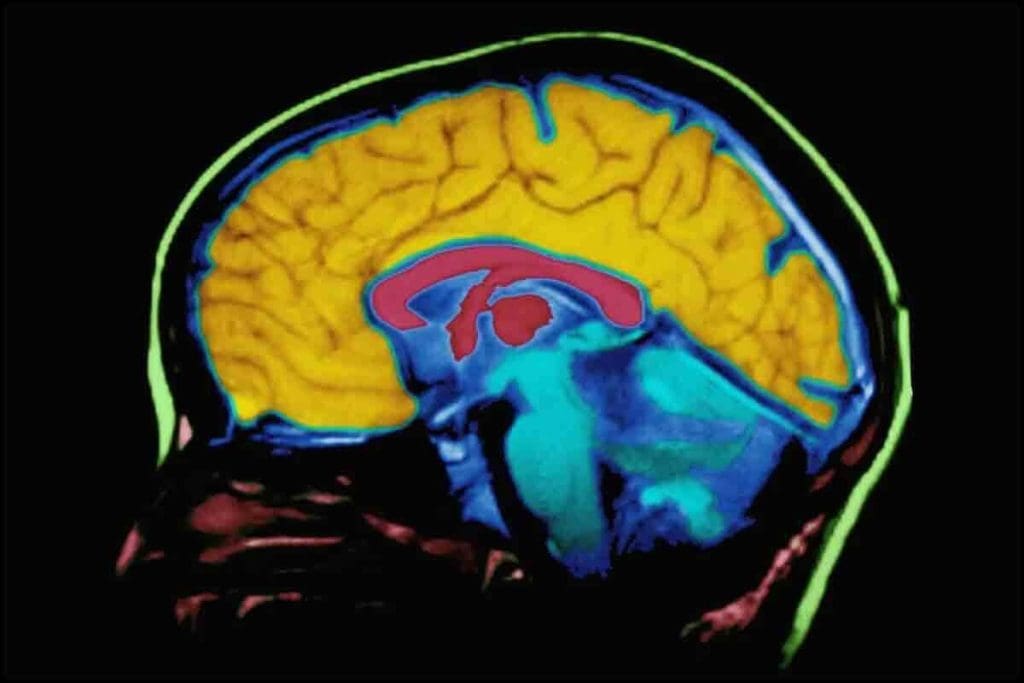

Brain imaging has changed neurology a lot. It lets doctors see the brain’s structure and function clearly. We use different brain imaging methods to find and treat brain problems. New tech has made diagnosing better.

How Neurologists Visualize Brain Structure and Function

Doctors use brain scans to see the brain’s details. Magnetic Resonance Imaging (MRI) and Computed Tomography (CT) scans show the brain’s shape. Functional MRI (fMRI) and Positron Emission Tomography (PET) scans show how the brain works. These images help find problems and plan treatments.